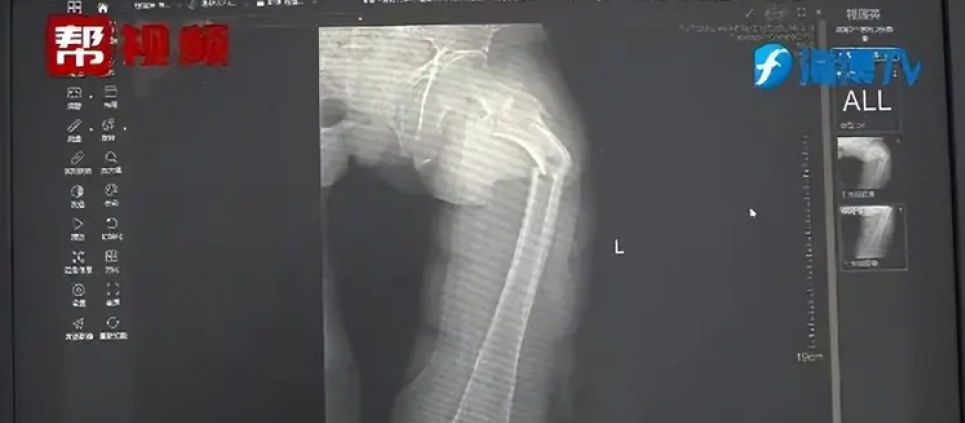

Рентгенівський знімок. Фото: Oddity CentralСтегнова кістка вважається найтвердішою чи другою за твердістю кісткою в людському тілі, але 35-річний чоловік у Китаї нібито примудрився зламати її, просто кашлянувши. Про це розповідає Oddity Central.

Рентгенівський знімок показав, що пан Є отримав перелом стегнової кістки, але його розповідь про кашель не мала жодного сенсу, і не було жодних ознак будь-якої фізичної травми. Чжун і його команда вирішили провести подальше дослідження, розпитавши пацієнта про його загальний стан здоров'я, харчові звички та спосіб життя, а також провели тест на щільність кісткової тканини, який дав тривожні результати. Щільність кісткової тканини Є була схожа на щільність кісток 80-річного чоловіка, що було незвично навіть для сучасних малорухомих чоловіків.